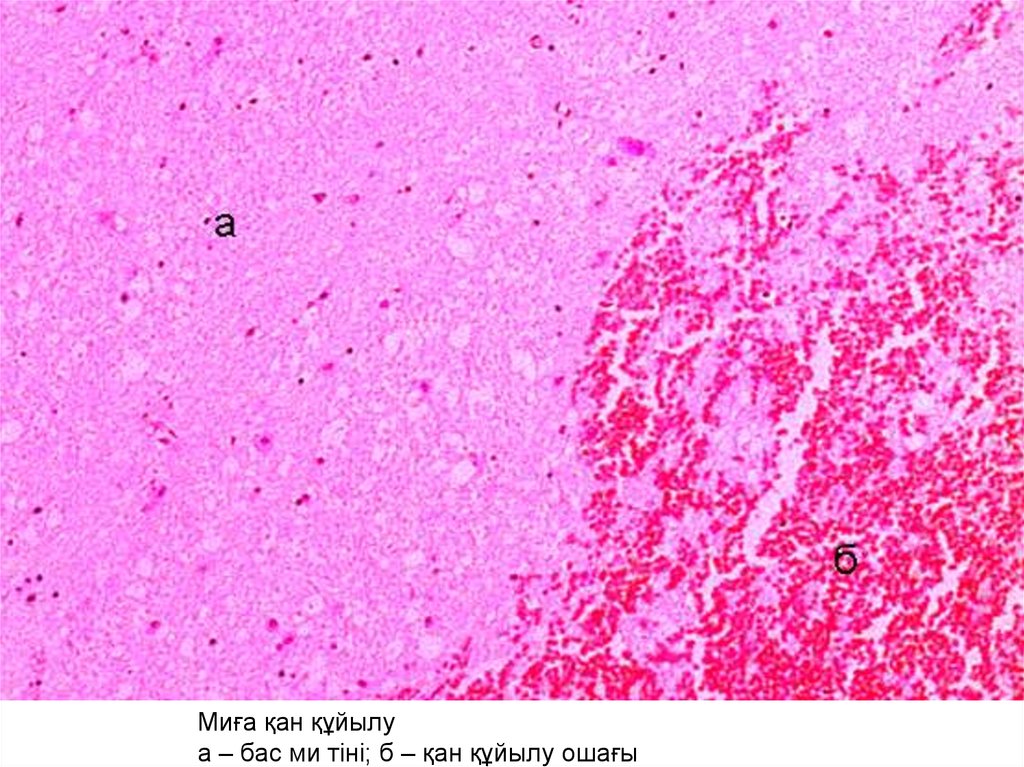

Миға қан құйылу

а – бас ми тіні; б – қан құйылу ошағы